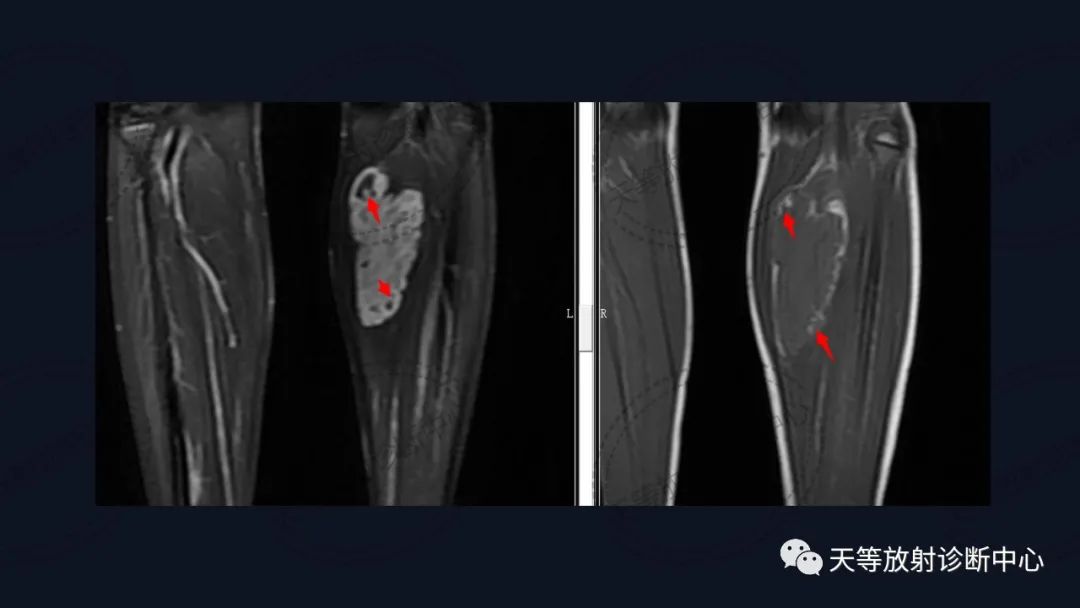

组织学上主要表现为血管管道数目的增加及纤维结缔组织、平滑肌、炎性细胞和毛细血管、淋巴管等不同程度的浸润。MRI观察病灶内纤维结缔组织呈分隔状及线状低信号影,含血管成分可表现血管流空信号影。病灶内出血表现信号混杂等。